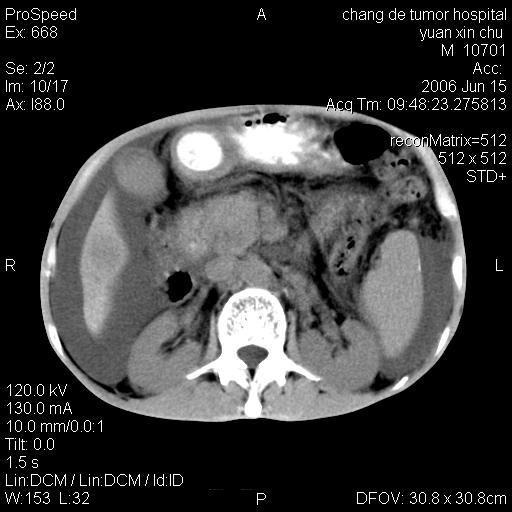

以下是引用qian在2007-4-23 19:06:00的发言:[br]胰腺体积增大,轮廓欠规则,肝轮廓波浪状改变,肝裂增宽,肝周、脾周有液性密度,腹膜后肿大淋巴结,考虑1、胰腺癌伴腹膜后淋巴结转移;2、肝硬化伴腹水。

以下是引用卜一在2007-4-23 20:12:00的发言:[br]胰腺体积增大,轮廓欠规则,肝轮廓波浪状改变,肝裂增宽,肝周、脾周有液性密度,腹膜后肿大淋巴结,考虑1、胰腺癌伴腹膜后淋巴结转移;2、肝硬化伴腹水。支持!